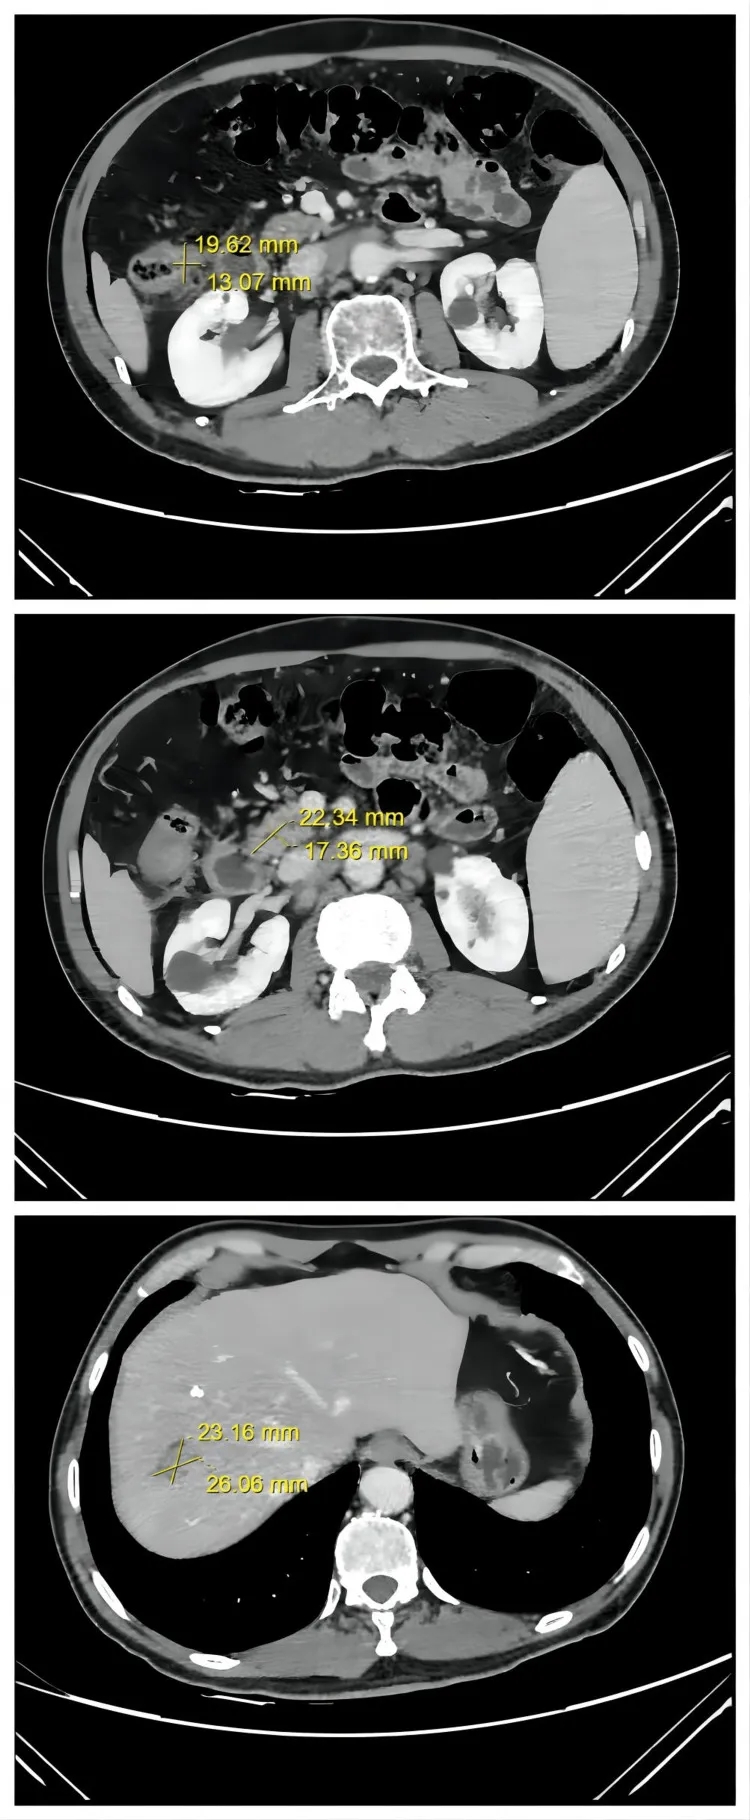

2、病灶全面缩小并达PR:相较于第二次治疗后“结肠及淋巴结病灶缩小、肝转移灶无变化”的情况,此次所有病灶均明显缩小——CT显示结肠肿瘤从3.7cm×3.1cm缩小至2.1cm×1.7cm,腹膜后淋巴结转移灶从5.2cm×4.3cm缩小至2.3cm×1.4cm,肝脏肿瘤从3.9cm×3.2cm缩小至2.9cm×2.3cm(详见下图)。肿瘤缩小至可手术切除的程度。术后,患者获得病理完全缓解(pCR)。

▼该患者第三次治疗后,腹部轴向CT图像